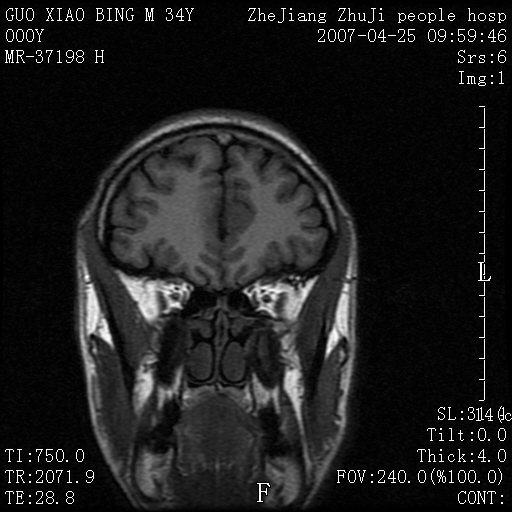

以下是引用qiuleiyu在2007-4-27 16:41:00的发言:[br]ct左侧额顶部囊性膨胀性骨质破坏,边缘有轻度硬化,其内示多发点条状高密度。[br]mri;t1低信号,t2明显高信号。界清。增强后明显强化。[br]综合考虑;颅内血管瘤。上传该病例,目的在于加深印象,共同学习。[br]骨血管瘤好发于颅骨及椎体。为良性肿瘤。组织学上分海锦型及毛细血管型。前者多见。[br]颅血管瘤典型影像学表现;[br]1,平片;类圆形骨质破坏,边缘硬化,内示中央向周边年轮状辐射(残存增粗骨小梁)。[br]2,ct;颅内板障内膨胀骨质破坏,边缘硬化,内示密集点状及放射状骨针影。[br]3,mr;t1、t2高信号。该病例t1不高可能与血流较丰富有关。边缘低信号。增强明显强化。[br]鉴别;[br]1,脑膜瘤;主要累及内板,与血管瘤发生于板障不同。颅板骨质增生硬化,与颅内垂直放射状骨针。与血管瘤日光放射状不同。增强可见脑膜尾征。[br]2,嗜酸性肉芽肿;起自板障溶骨性骨质破坏。内无点状及放射状高密度影。边缘硬化不明显。局部可有骨膜反应。[br]3,转移性肿瘤;溶骨破坏边缘模糊,无硬化边。发展迅速。有原发肿瘤史。可多发。可出现软组织块。[br]4,单发骨髓瘤;发病年龄较大,临床可能全身骨质疏松,骨痛。免疫球蛋白增高。部分病例本周氏蛋白可增高。可有边缘硬化,然内无点状高密度影。[br]